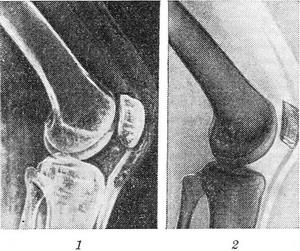

Электрорентгенография (синонім ксерорадиография) - метод рентгенографії, заснований на сухому (чи фізичному) спосіб фотографування. У цьому методі приймачем рентгенівського випромінювання служить не рентгенівська фотоплівка, а тонкий шар селену, нанесений на алюмінієву або латунну пластинку, яка поміщена в касету. В такому стані селеновая платівка нечутлива до рентгенівського випромінювання. Электрорентгенограмма характеризується високою контрастністю і різкістю, що дає можливість краще, ніж на звичайній рентгенограмі, виявляти структуру кісткових і навіть м'яких тканин (рис. ); вона може бути отримана за 2 хв.; відпадає необхідність в затемненні; одна селеновая платівка може бути використано до 1000 разів.

![]() Электрорентгенограмма (1) і рентгенограма (2) колінного суглоба. |